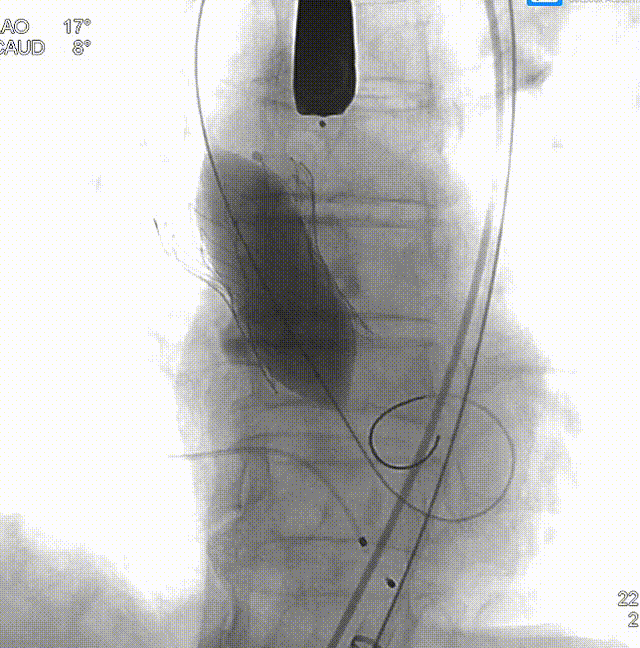

相应的手术策略:

• 右侧股动脉为主入路,左侧辅助入路,使用20F血管鞘;

• 跨瓣角度为LAO 17° CAU 8°(右窦中心位)左右,使用22mm球囊预扩张,球囊预扩角度为LAO 17° CAU 8° (右窦中心位)左右;

• 预装AV26瓣膜,释放角度RAO 11° CAU 32°(左右重合)左右,较高位释放(瓣环下0-2mm)。释放后调整至左前斜头位( LAO 35° CRA11°)进一步确定人工瓣膜形态。手术结束后造影评估入路血管情况,避免遗漏血管并发症情况。

手术过程

主动脉根部造影,少量反流,采用22mm球囊预扩,轻微腰征,造影微量瓣周漏。

主动脉根部造影

球囊预扩

TaurusElite 输送器轻松过弓、跨瓣,TaurusElite AV26精准定位无冠窦最低点。

TaurusElite柔顺过弓

瓣膜定位